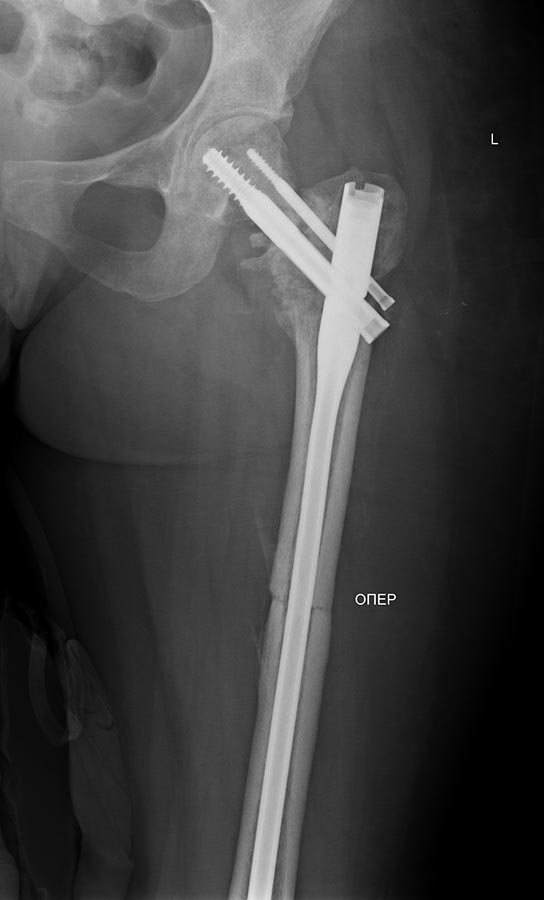

Сегодня сделали левое бедро. Сделана аналогичная чрескожная

вальгизирующая остеотомия, закрытый интрамедуллярный остеосинтез

Affixus.  Длинным, с учетом еще и бывшего диафизарного перелома. Были

какие-то мысли насчет пластики дефекта шейки - решили воздержаться.